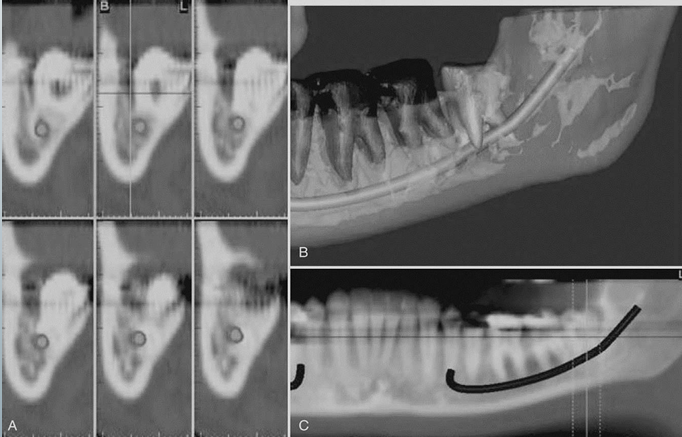

CBCT for implant site assessment

-curved planar MPR (multiplanar reformatting) accomplished by aligning the long axis of the imaging plane with the dental arch in A

-provides a region panorama-like thin-slice image in B

-serial thin-slice transplanar images are often generated (C), which are useful in the assessment of specific morphologic features such as the location of the inferior alveolar canal for implant site assessment and for allowing measurement of the available alveolar bone height and width

use of a diagnostic stent

-providers fabricate a diagnostic stent or radiographic guide, depending on the case

-stents provide fiducial radiographic landmarks that can be used to correlate the proposed clinical location and angulation of implants with the available alveolar bone

-pan projection in A provides an overview of the location

-serial cross-sections in B indicate alveolar bone height